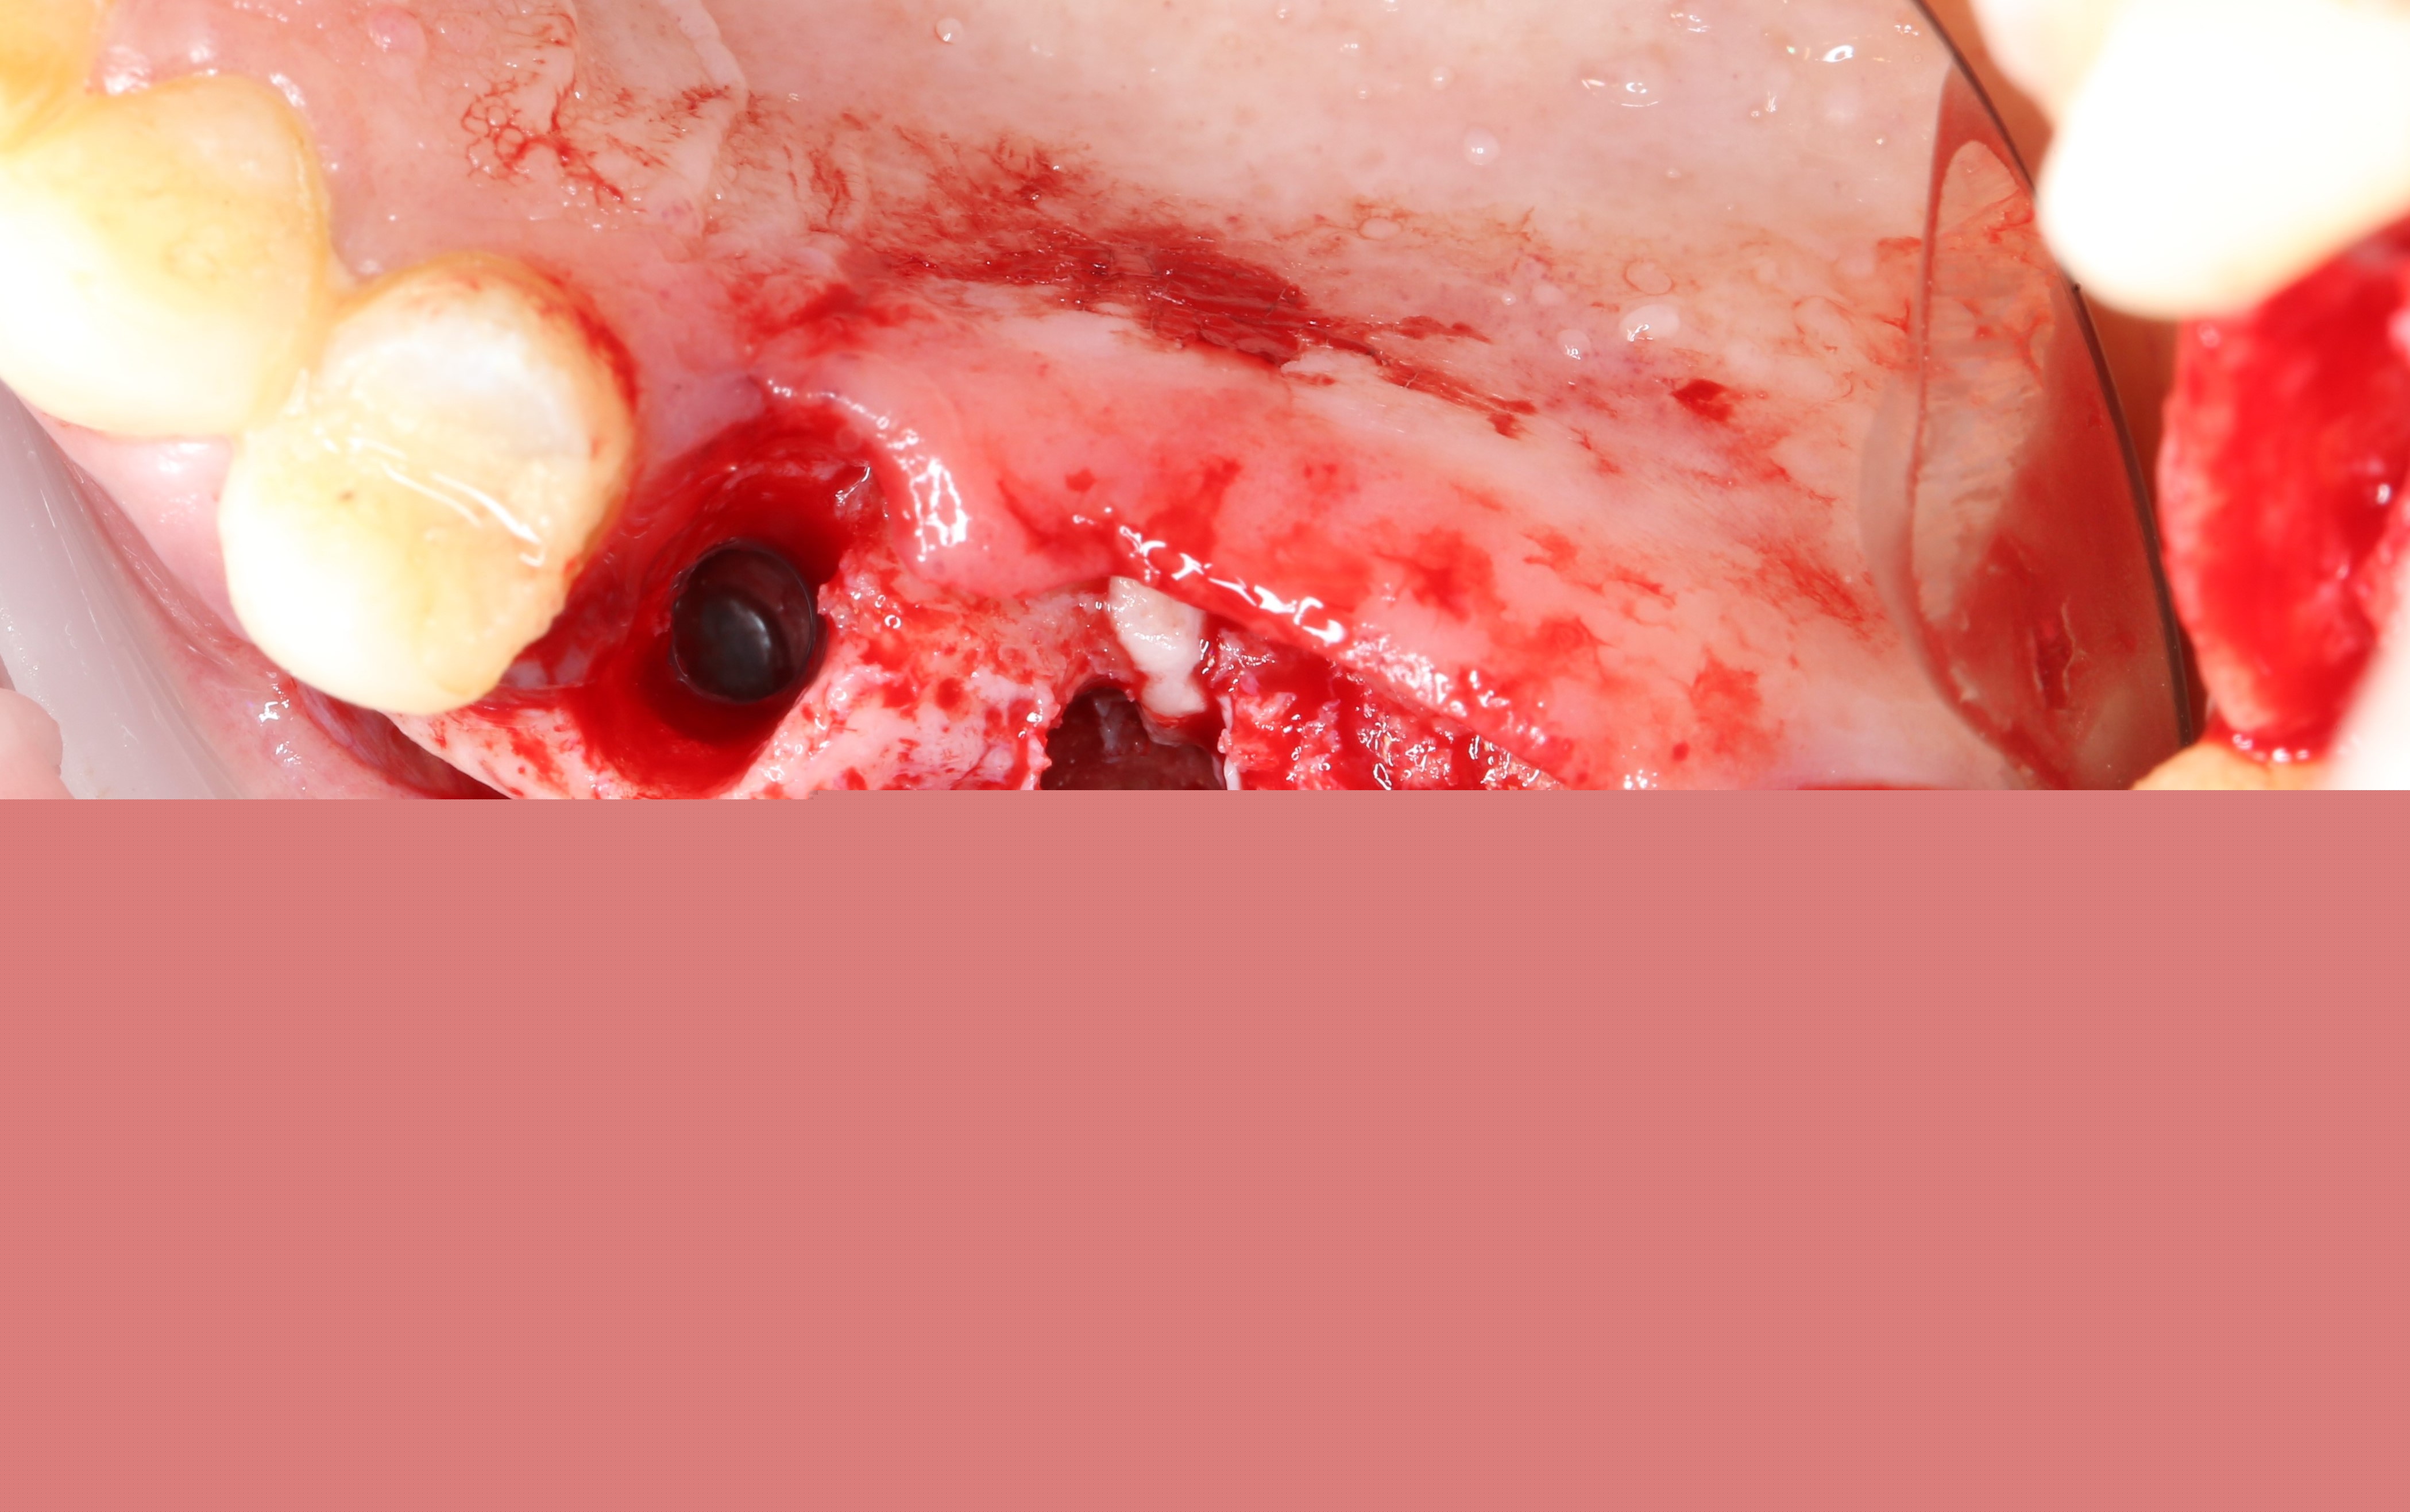

В сформировавшийся карман укладывается гемостатическая губка, смоченная в физ. растворе:

Это необходимо для того, чтобы не повредить слизистую в момент формирования ложа под имплантат сверлом.

При помощи наконечника с охлаждением и фрез повышающего диаметра формируются ложа под имплантаты. С этапами установки имплантата вы можете ознакомиться в статье: «Установка имплантата: как это делается?»

При помощи аналога (пина) имплантата контролируем параллельность.

Вид сверху: